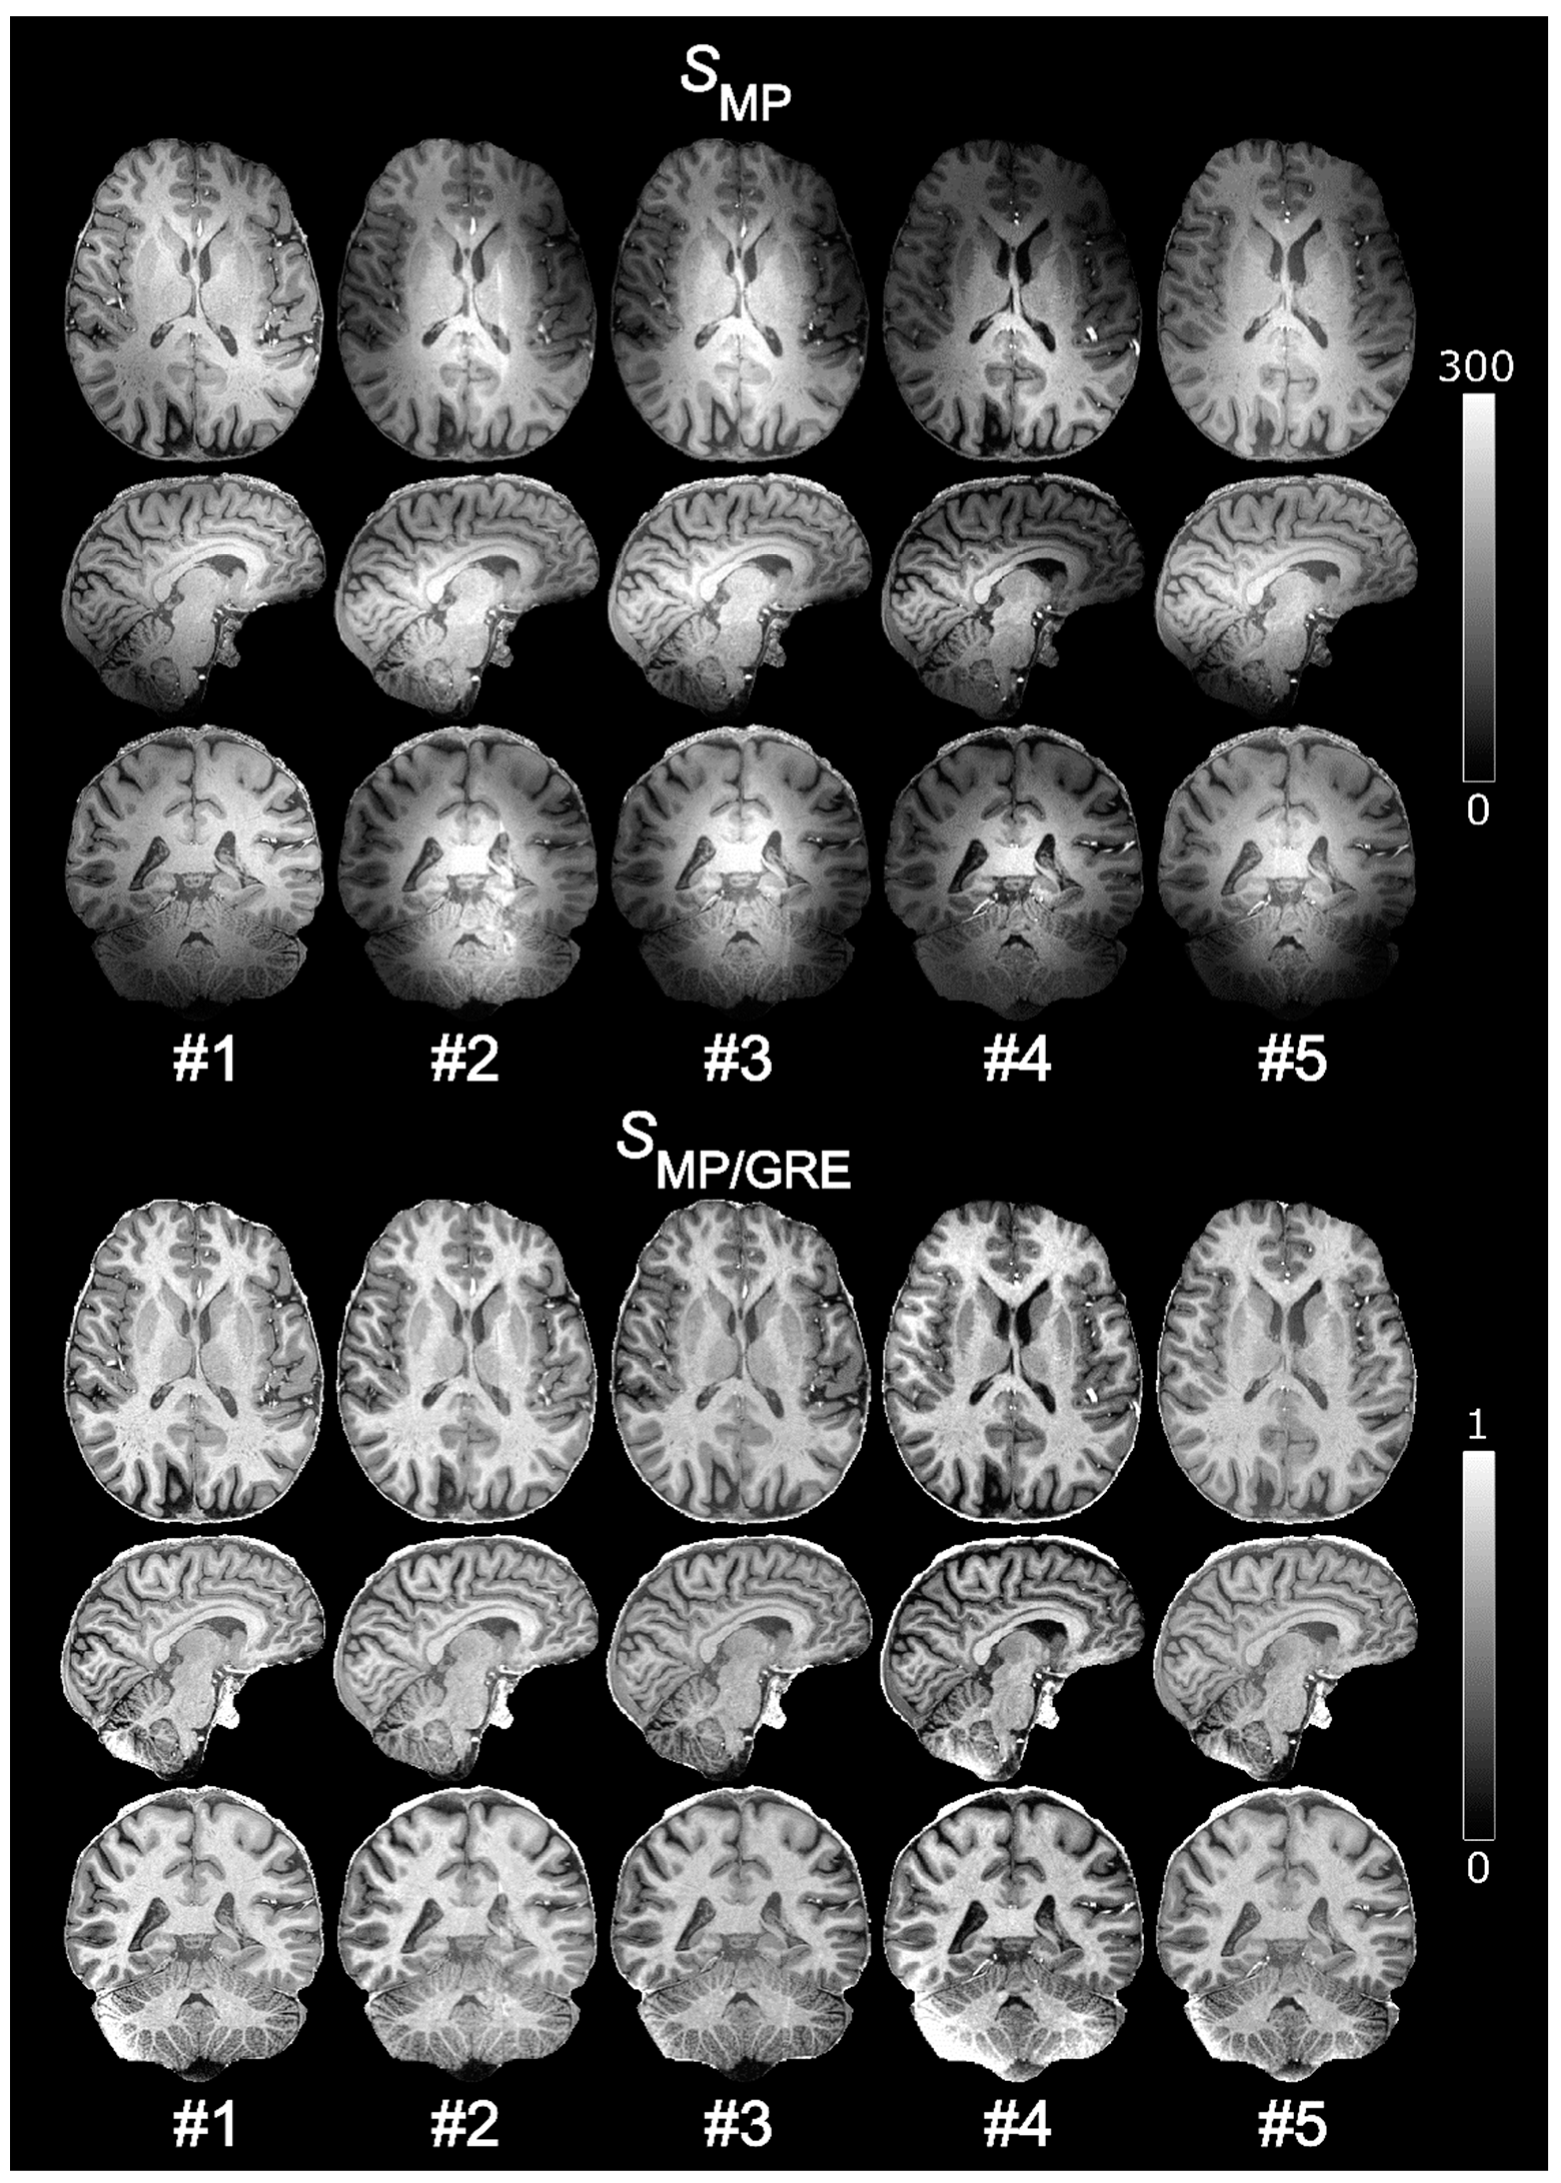

3.1. Readout Flip Angle of Reference GRE

There was a continuous decrease in tissue contrast in the normalized volume as αGRE increased (Figure 1). This decrease was evident both from visual inspection (for αGRE > 3°) and from the quantitative comparison of segmented WM and GM (panel C). The contrast was still increased after normalization, compared to before, for all values of αGRE. The ROI analysis (panel D) showed no decrease in CV, neither at lower αGRE nor after normalization, and no apparent change in SNR could thus be identified. However, a minimum in the CV of segmented WM (panel E) was observed at αGRE = 3°, implying minimal influence of residual B1+ inhomogeneities at this setting. The B1+ influence was visually identifiable as elevated pixel values in the center of the brain using αGRE = 6° (panel B). Based on these results, and to avoid deviating too far from the Ernst angle (~7°–5° for 1000 ms ≤ T1 ≤ 2000 ms), αGRE = 3° was deemed optimal and chosen for the final protocol. At αGRE = 3°, the WM-GM contrast was C = 0.18 and the variability across segmented WM was CV = 9% after normalization compared to C = 0.10 and CV = 34% before.

Figure 1. Reference GREs with different αGRE (top row, (A)) used to obtain normalized MPRAGE volumes (middle row, (B)). Decreasing WM-GM contrast with increasing αGRE is evident from visual inspection of the normalized volumes and verified in the scatter plot (C). No change in SNR could be identified by the CV in a WM ROI (red circle) (D). The CV in whole segmented WM had a minimum at αGRE = 3°, implying minimum influence from residual B1+ effects (E). These residual B1+ effects are visually identifiable as hyperintense pixels in the center of the normalized MPRAGE for αGRE = 6° (B). The solid lines in the scatter plots represent the respective MPRAGE volume values before normalization. In this experiment, the dielectric pads caused a visible fold-over artefact (red arrow).